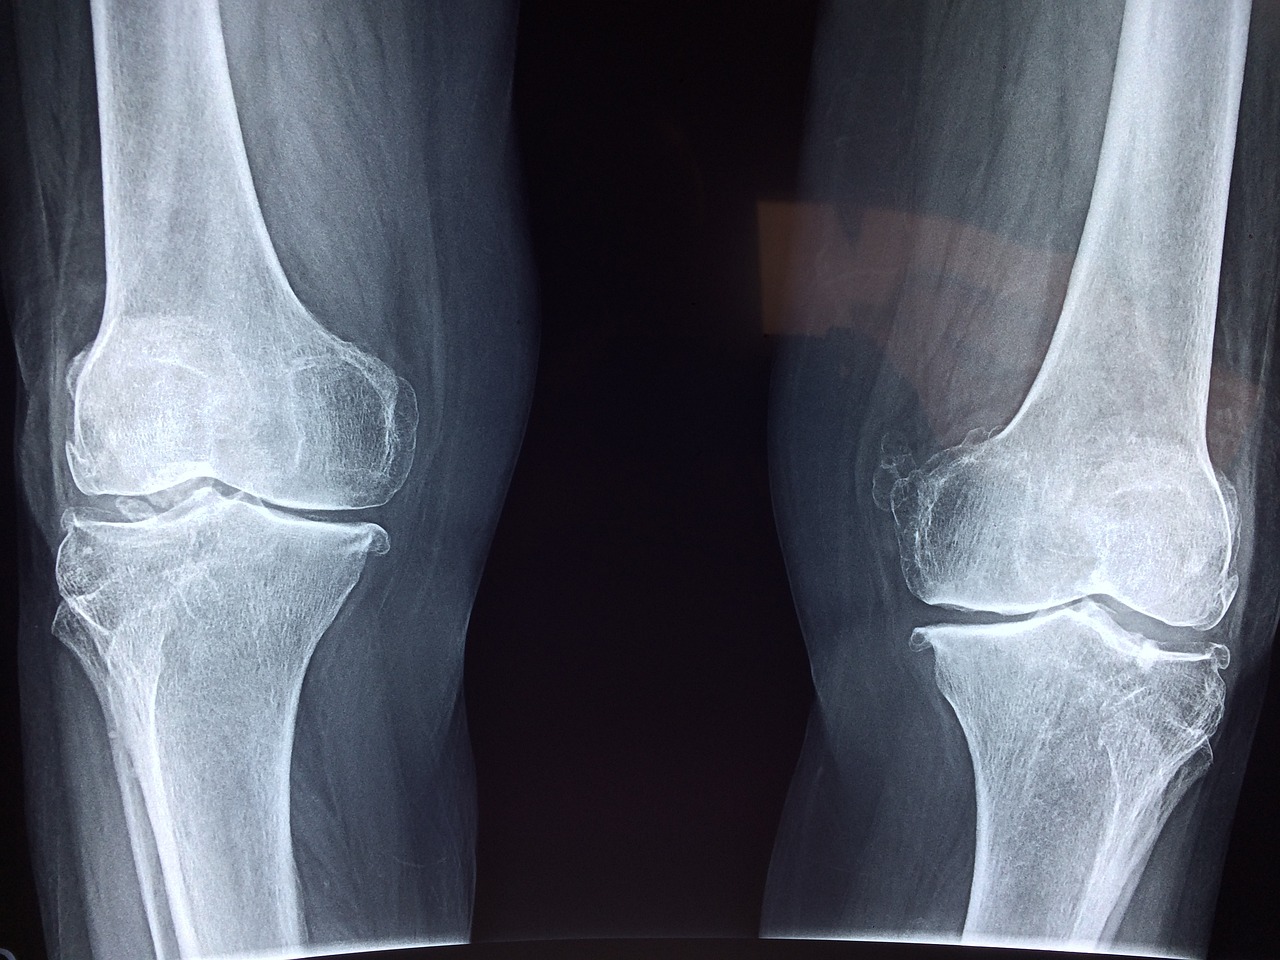

콘드로이친은 관절염 증상을 완화하는 데 도움을 줄 수 있어요.

관절 연골을 보호하고, 마찰을 줄이는 역할을 해요.

염증 반응을 억제해 통증을 줄이는 데에도 효과가 있어요.

특히 무릎, 손목, 허리 등 다양한 부위의 관절 통증 관리에 도움이 돼요.

몇몇 연구에서는 콘드로이친 복용이 퇴행성 관절염 진행을 늦춘다고 보고되었어요.